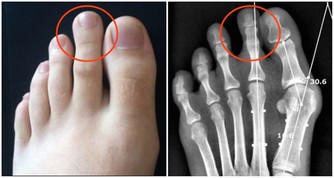

痛風,是因為人體內血液中的尿酸水平過高導致的,是尿酸鹽沉積在組織內引起的疾病。體內尿酸水平升高,主要有兩大原因,